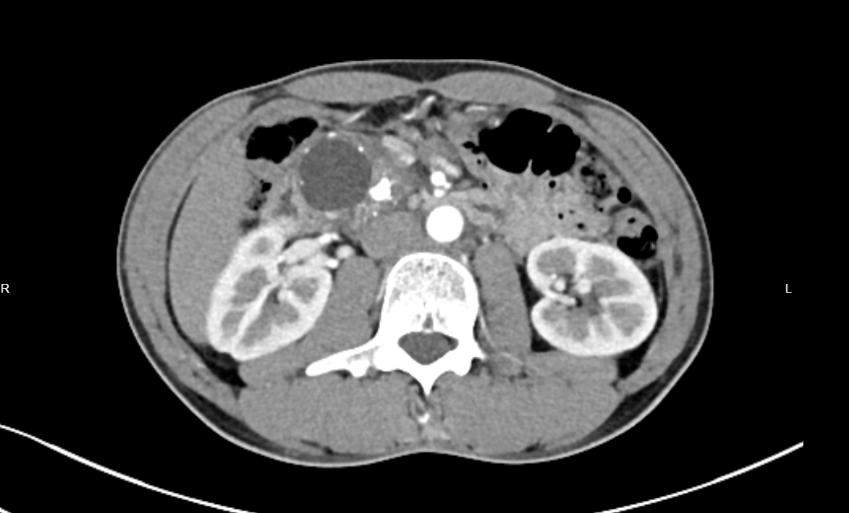

(图一:胰头部占位)(图二:胰腺多发结石)

最新一例患者是49岁男性王先生。 他长期饱受胰腺炎、糖尿病困扰,近期因上腹不适检查发现胰头部囊性肿瘤、胰腺结石及慢性胰腺炎急性发作。传统手术需切除十二指肠、部分胃及胆道,创伤大、恢复慢。相比传统切除术,保留十二指肠的胰头切除术(DPPHR)创伤更小、恢复更快、术后生活质量更高,但技术难度极大——稍有不慎就可能导致十二指肠缺血坏死或胆管损伤,因此对主刀医生的解剖功底、精细操作能力要求极高。